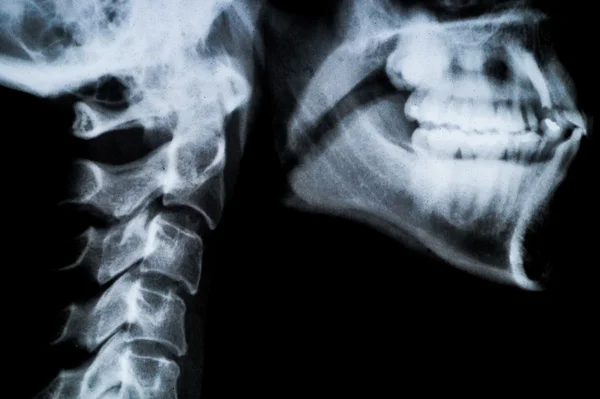

в задней прямой проекции через рот . . . . с функциональными пробами: что показывает, как делают, цена, снимок, норма, фото . . . . делают снимок в максимальных фазах сгибания и разгибания шеи . Снимок . . .

Шейный остеохондроз фото рентген до и после . . . Принцип работы и виды рентгена шеи . . . . поэтому для их оценки производят дополнительный снимок через открытую ротовую полость . Назначением . . .

Даже если процедуру проводят через рот, то на рентгене будет видно следующие проблемы, нарушения, связанные с шейными позвонками: Травмы шеи за счет появления микротрещин;

Боли при движении функциональных отделов шеи . Фото рентгена с функциональными пробами: . . . Рентгенография шейных позвонков через рот назначается малышам только с трех-четырех лет, но . . .

Детям старше 3-4 лет может быть назначена такая процедура, как рентген через открытый рот . Некоторые мамы ее пугаются . Однако это тот же снимок, только сделанный при широко открытых челюстях .

Чтобы получить качественное изображение, потребуется сделать прицельный снимок через открытый рот пациента . Как правило, назначается процедура рентгена шейного отдела позвоночника в . . .

Снимок через рот и 2 заключения рентгена прилагаю . Фото снимка, наверное, не очень хорошего качества . Если по нему нельзя ничего понять, я могу попробовать переснять Заранее спасибо . Возраст: 25